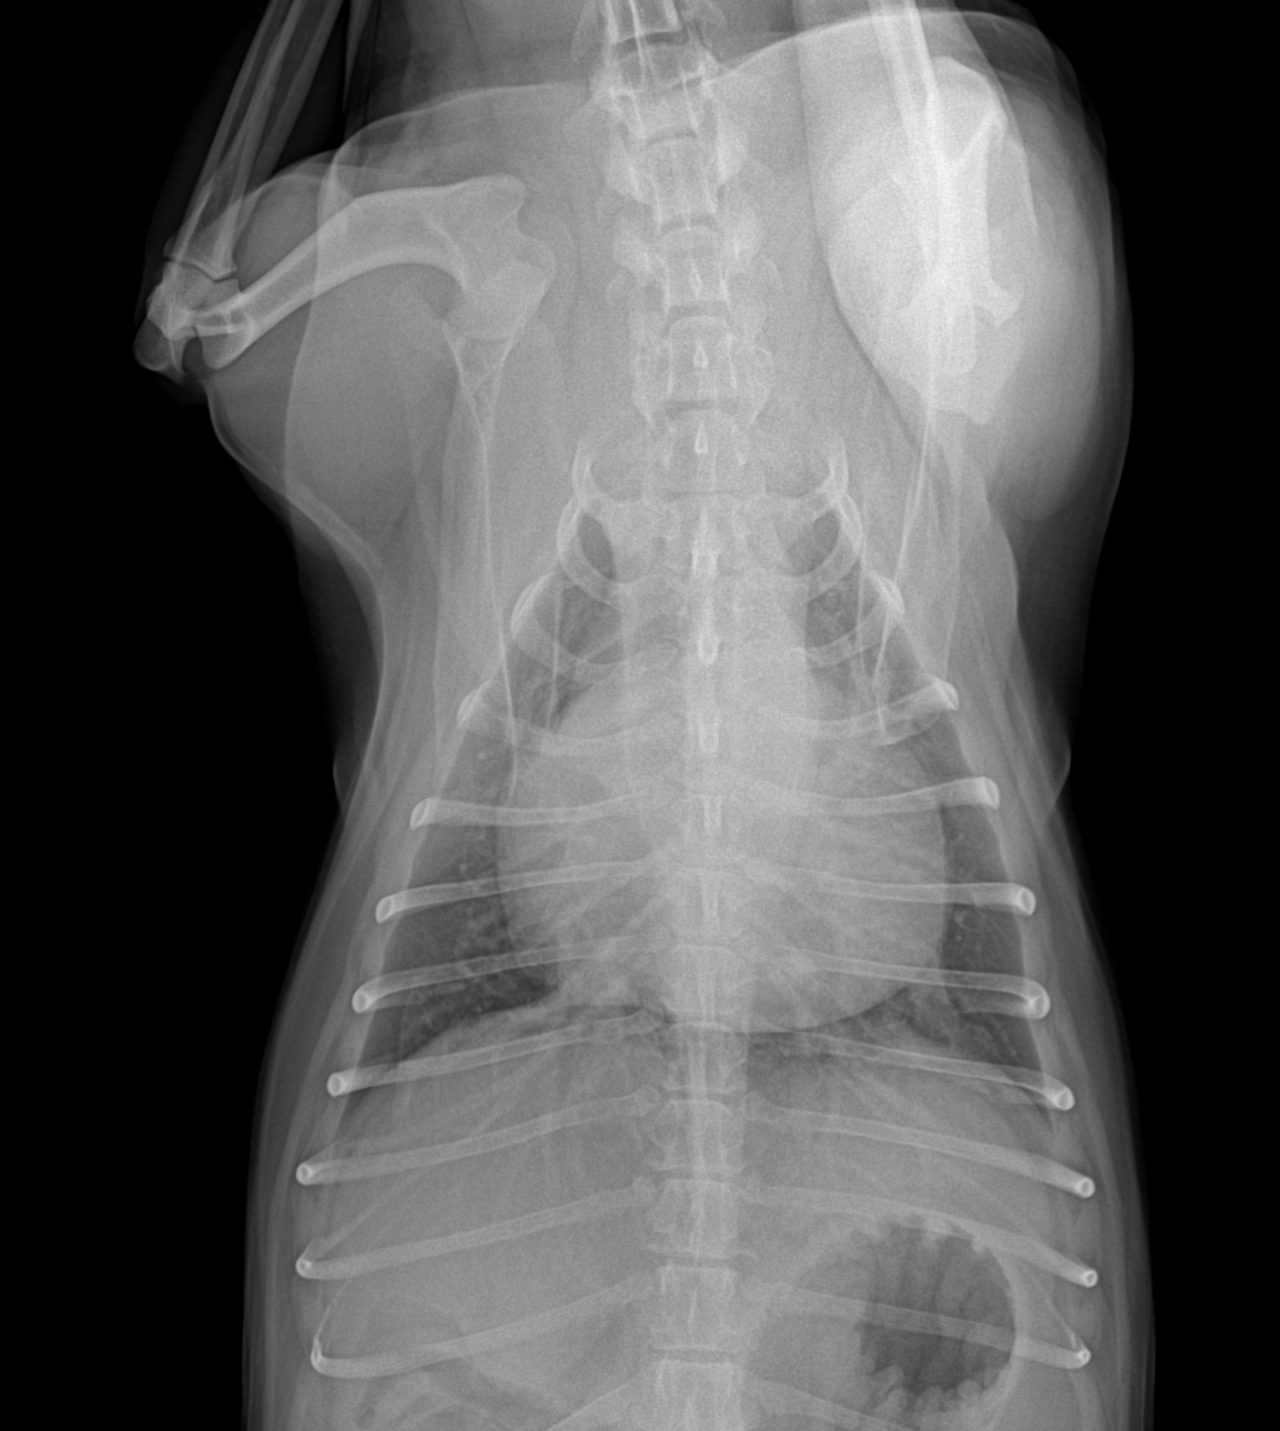

9歳の柴犬が散歩中に突然倒れる事があるとのことでかかりつけを受診しました。幼少時よりてんかん発作を発症する事があるが、今回の様子はてんかんの時とは異なる様だとのことで精査を希望され来院しました。心音は微弱でマッフルを呈していました。また、腹水の貯留も確認されました。心臓超音波検査では心膜液の貯留が確認されました。心嚢水の除去を行なったところ、出血性の心嚢水でした。数日間は心嚢水の除去のみで一般状態は改善していました。しかし、再発すると虚脱するといった症状が確認されたため、再発性の心タンポナーゼを回避するために、胸腔鏡下で心膜切除術を実施しました。同時に中皮腫、血管肉腫、特発性との鑑別にCTによる精査も実施しております。心膜の病理検査では腫瘍性の変化はなく、著しく繊維化した心膜であり、特発性と診断されました。胸腔鏡下での手術であったため、数日間の入院で痛みも少なく良好に経過しています。